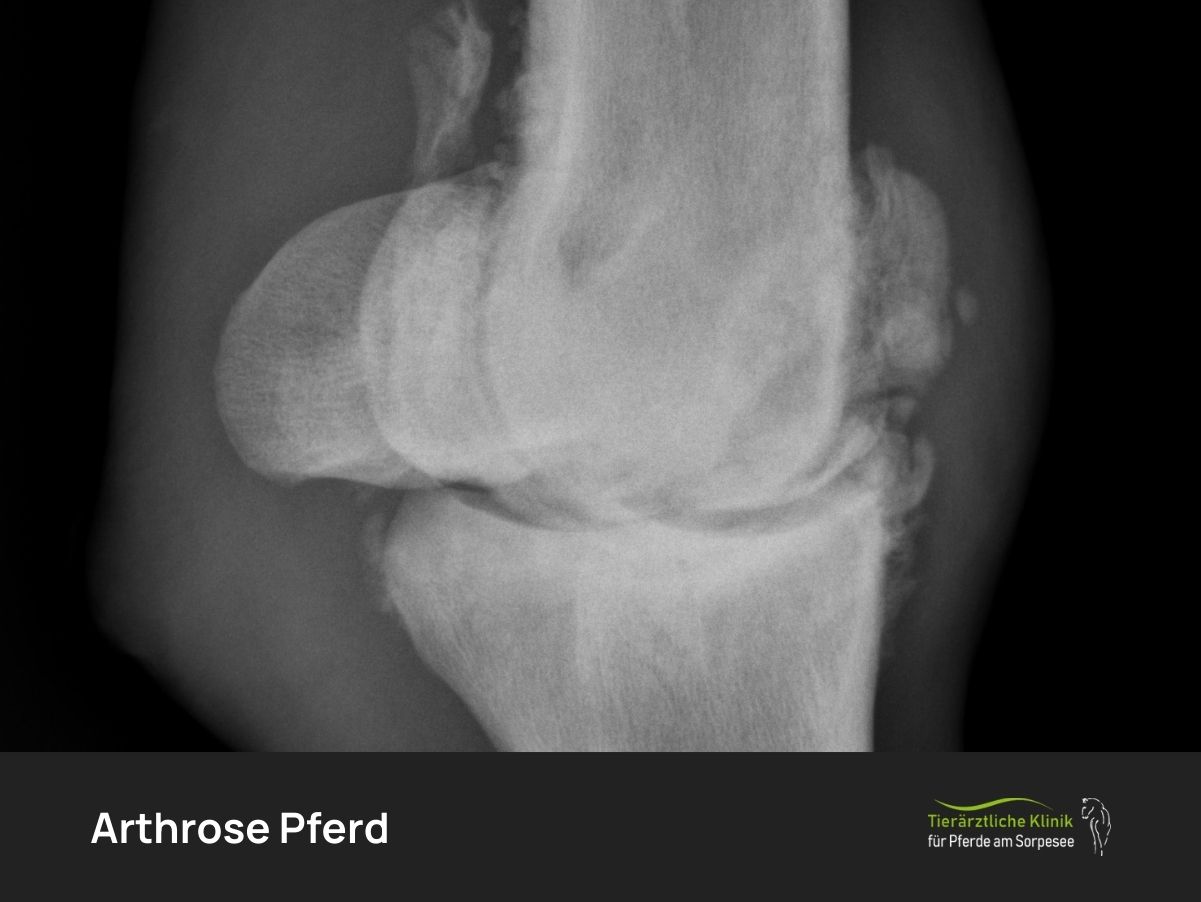

Rückenschmerzen beim Pferd sind ein häufiges und wichtiges Symptom für Überlastung, Bewegungsmangel, Fehlhaltungen oder Erkrankungen des Bewegungsapparats. Rückenschmerzen treten beim…